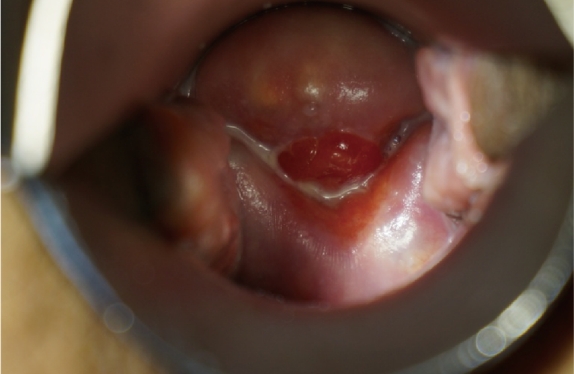

Effect of Laser Treatment Collagen Stimulation

- Vaginal Remodeling

- Vaginal Dryness

- Sexual Dissatisfaction

- Pelvic Organ Prolapse

- Urinary Incontinence

Before

Harmful Bacteria

After